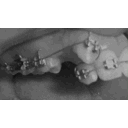

image.jpg